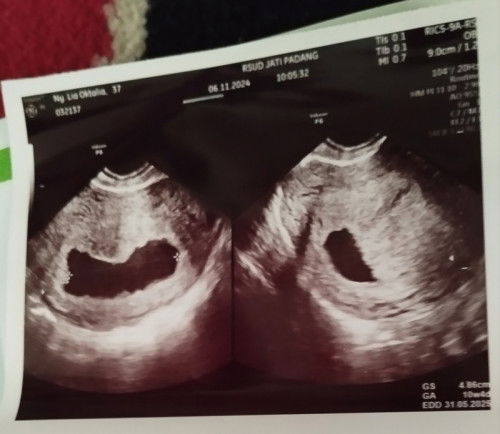

Abis usg, kata dokter suspek BO..

Mudah²an diberi jalan keluar yg terbaik dr yg paling terbaik dr Allah SWT.. Aamiin..